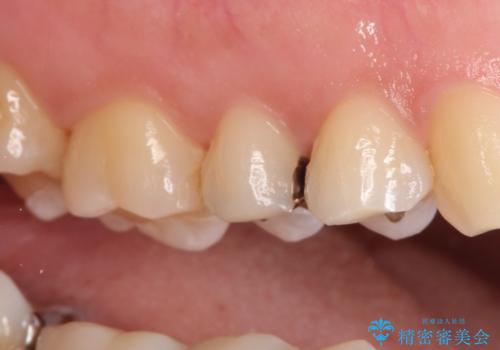

- 金属の詰め物を外して、セラミックインレーを入れたいと来院された患者様です。

奥歯に虫歯も認め、3歯の治療を来院回数2回で終了で終了しています。